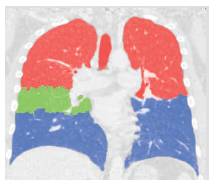

5. Method

A lobe segmentation method is developed which combines anatomical information from the lungs, vessels, airways, and lobar fissures to obtain the lobes using a Atlas method as in Figure 8. The approach is an extension of the framework of Bianca [9]. The method starts by segmenting the lungs, vessels, airways, and fissures, which are later combined into one cost image. In the first step lungs are segmented since all other segmentations are only performed inside the lung regions. A good lung segmentation is a prerequisite for the here presented lobe segmentation approach. The lung segmentation applied achieved the best performance in the LOLA11 [10] challenge.

Figure 8. After the application of Atlas method final lungs, Fissures and lobe segmentation